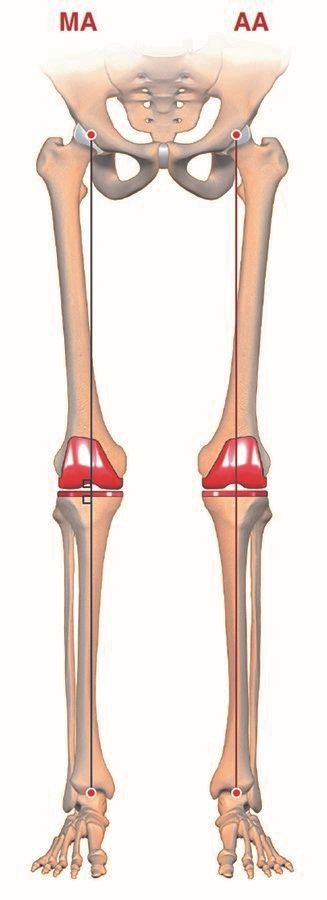

Anatomical alignment (AA)

The anatomical alignment (AA) technique (Figure 5), first introduced in the 1980s by Hungerford et al., represents only a modification of the MA concept. The target is also a neutral mechanical axis for all knees but creating an oblique joint line (2°–3° of varus). Nevertheless, it represents also a ‘systematic approach’ like MA (i.e. identical for each patient irrespective of native anatomy).

The technique is designed to reproduce the natural knee joint line obliquity with frontal bone cuts of femoral valgus 3° and a tibial varus 3° and to optimise patellar biomechanics by minimising any changes to the native distal femoral anatomy. However, this school of thought never took hold due to the technical difficulties in the 1980s of achieving accurate bone cuts. For most of the surgeons the risk of producing excessive (>3°) and presumably harmful varus of the tibial implant did not compensate the possible advantage of this more anatomical alignment concept. Nowadays, this lack of surgical precision has been overcome in two ways, namely the use of precision tools for implant positioning (navigation systems and robotics), and the development of TKA implants incorporating a 3° joint line obliquity in their design, which allows the surgeon to obtain an oblique femorotibial joint line using mechanical bone cuts (‘AA-like technique’). Good mid to long-term results have been published with both techniques (AA and AA-like) (8,9) but in two recent RCT studies no difference could be identified in comparison to the MA technique.